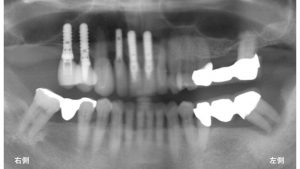

以下がインプラントを埋入した当日のレントゲンです。

使用したインプラントはストローマンインプラントです。